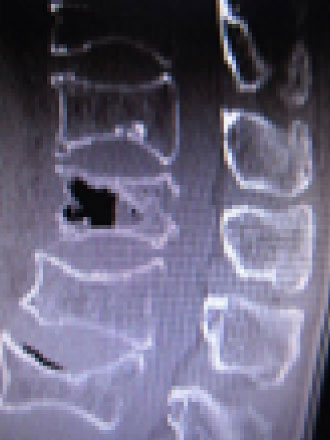

脊椎圧迫骨折手術

脊椎圧迫骨折に対する新しい治療法BKP(バルーンカイフォプラスティ) / 経皮的椎体形成手術

骨粗鬆症による、脊椎圧迫骨折(偽関節)の治療のための、新しい治療法

背骨の中が空洞になって痛みの原因になる場合があります。

通常、骨折は仮骨形成し骨が治癒していきますが、中に偽関節といって骨がつかない状態がまれにみられます。この場合、脊椎では椎体の中に空洞ができてしまいます。これによって、椎体内が不安定な状態になり、痛みがとれず長時間すわれないなどの症状がでます。

ほとんどの圧迫骨折では、コルセットやPTHの造骨促進治療で治癒しますが、この状態になると、待っても改善しにくく時間だけが経過し患者さんが無駄に時間を費やし不利益になることが予想されます。この場合、椎体の中の空洞にセメント注入し除痛をはかります。